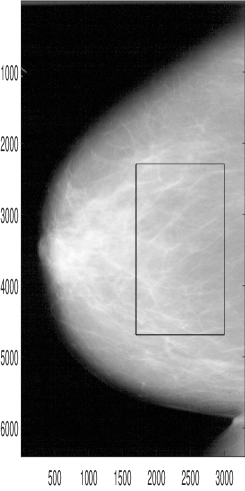

The digital mammogram analyzed comes from the Digital Database for Screening Mammography (DDSM) at the University of South Florida. The image is digitized by HOWTEK scanner at the full 43.5-micron per pixel spatial resolution and features craniocaudal (CC) projection. A detailed description of the data can be found in Bowyer et al. (1996).

Refer to caption

Figure 8: A ROI in a mammogram image selected for the estimation of scaling.

Figure 8 shows the location of the region of interest (ROI) within the mammogram. We selected the ROI of size 2401×1301240113012401\times 1301 and transformed it to a scale-mixing 2-D non-decimated wavelet domain. The spectral slope is estimated from the levelwise log-average squared coefficients along the diagonal hierarchy of multiresolution spaces, comprising the wavelet spectra, as in Figure 9. The slope of 2.67222.6722-2.6722 gives the Hurst exponent of (slope+2)/2=0.3361𝑠𝑙𝑜𝑝𝑒220.3361-(slope+2)/2=0.3361. Details can be found in Kang (2016) who use the Hurst exponent estimators to classify the mammograms from the DDSM data base for breast cancer detection.